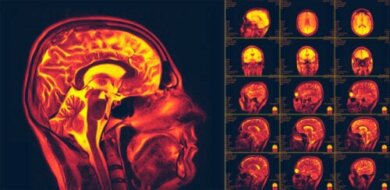

Bildgebende Verfahren und die Stimulation dieser Patienten konnten schließlich die Neuroplastizität nachweisen. Weitere Forschungen über die genauen Mechanismen, die dabei zum Einsatz kommen, werden derzeit an verschiedensten Forschungseinrichtungen durchgeführt.